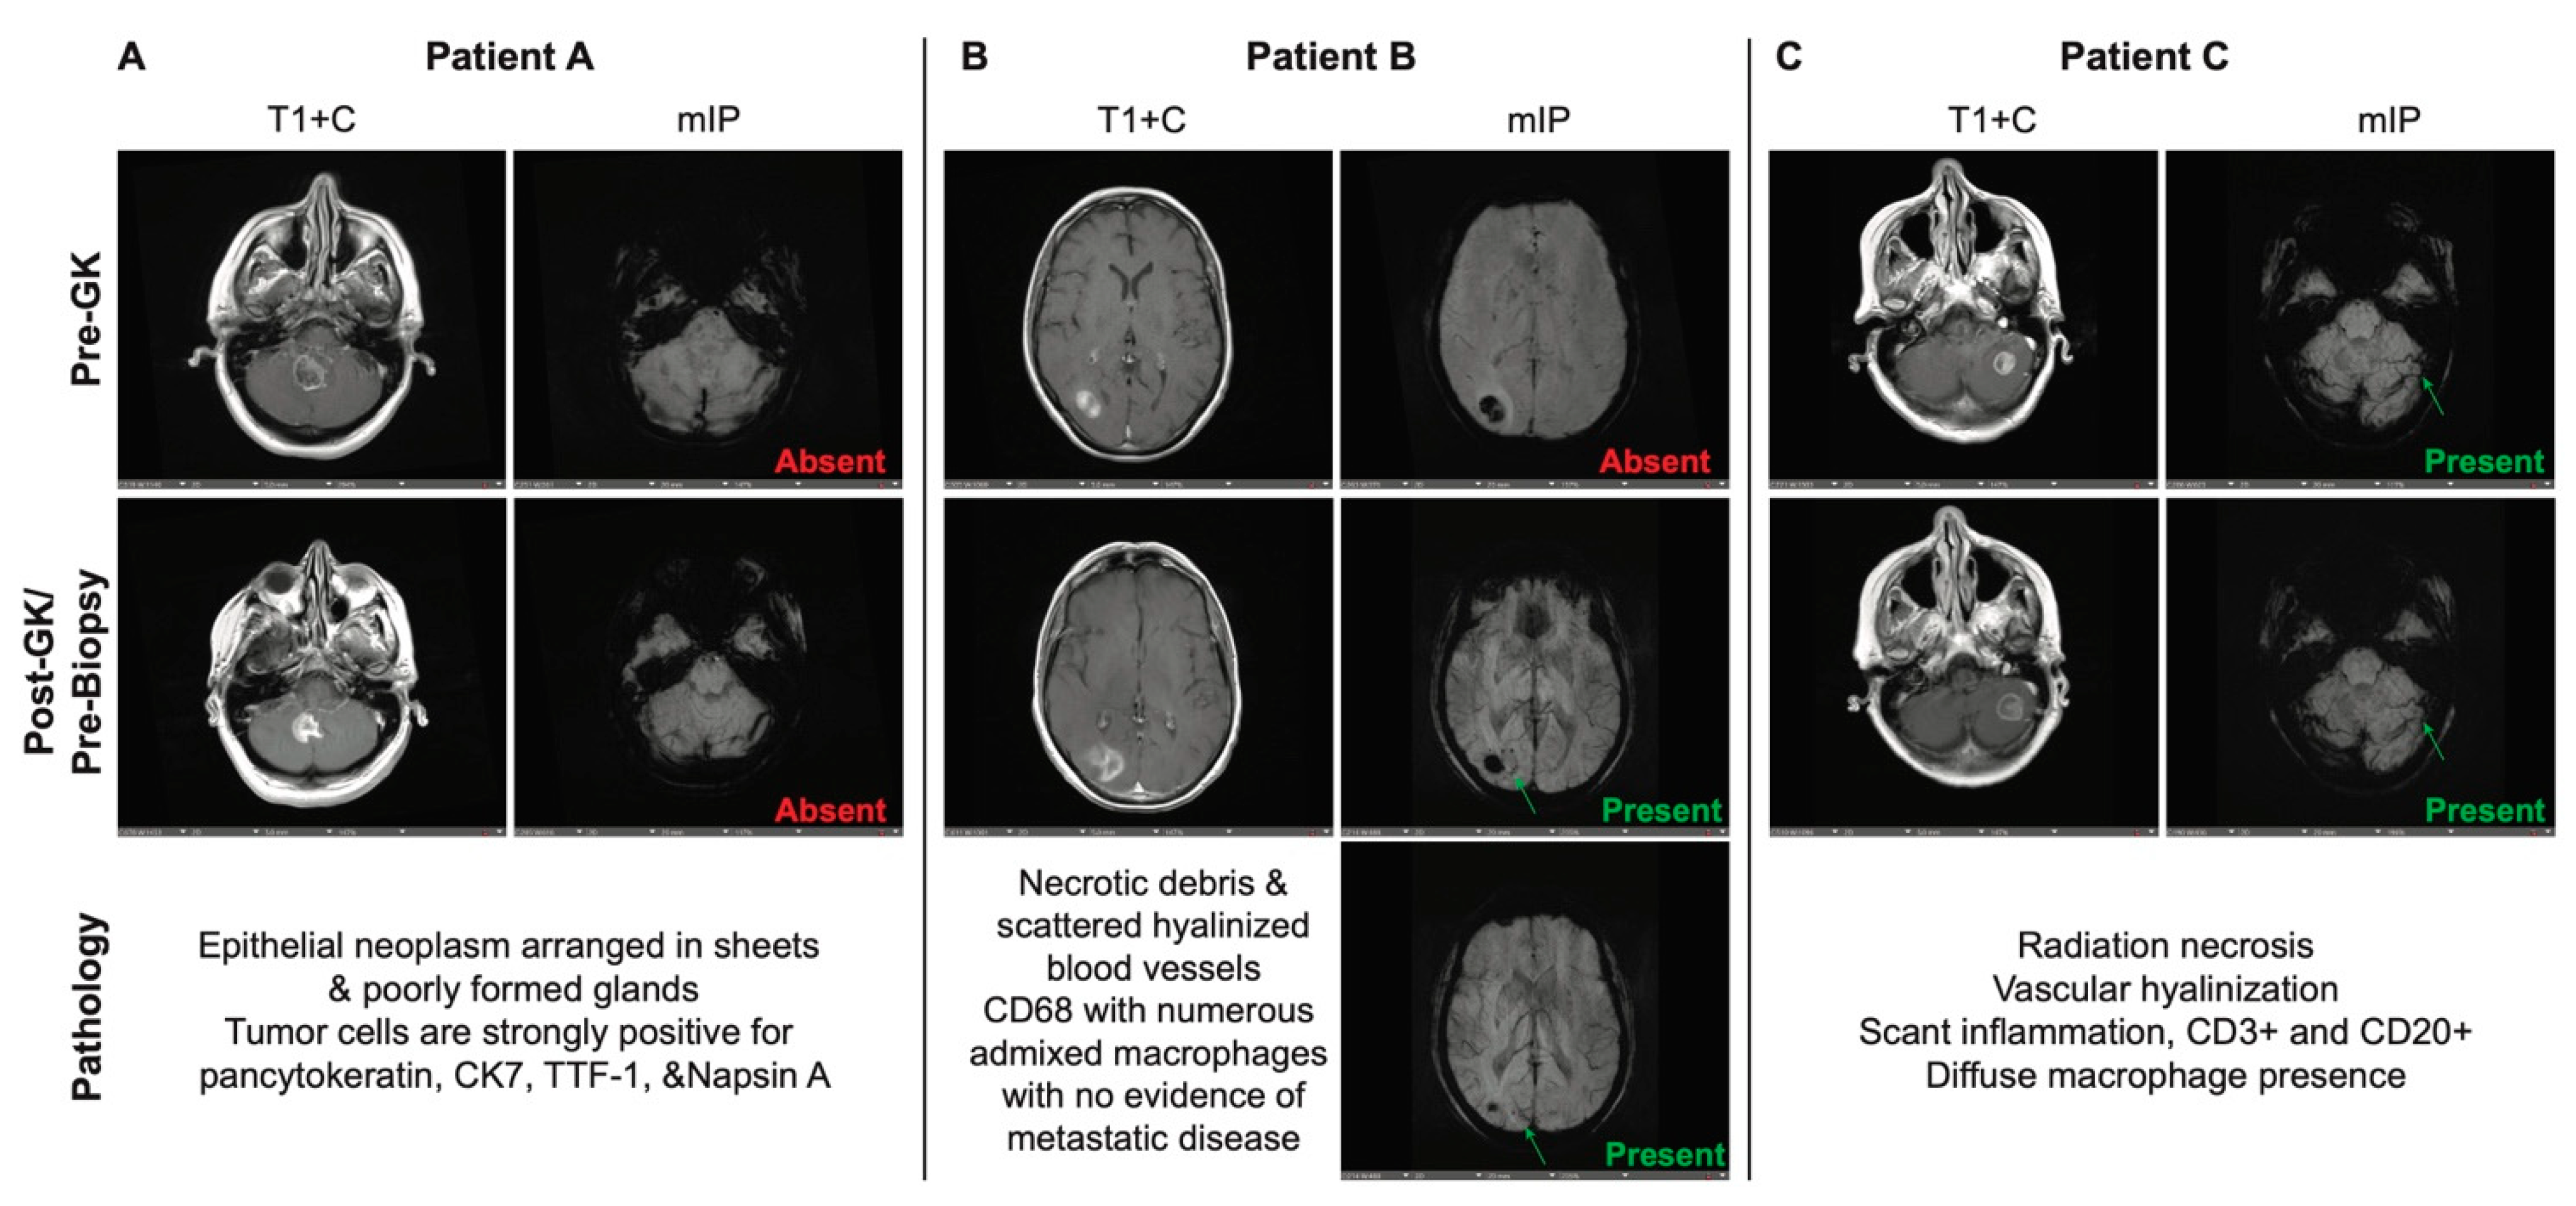

Susceptibility-weighted images using minimum intensity projection (mIP) were evaluated by two independent researchers to look for and identify CVS (Figure 1a-p). The findings were validated by an independent neuroradiologist. Of the 52 patients with post-biopsy diagnosis of RN alone across all tumor subtypes, 31 (60%) were found to have a pre-biopsy CVS on MRI. There were 14 patients that were found to have predominantly radiation necrosis with few residual tumor cells on histology; of these, 12 (86%) had a pre-biopsy CVS present as well. Of the 14 patients with a post-biopsy diagnosis of TP, only 3 (21%) had CVS on MRI. We performed Fisher exact tests and multivariate logistic regression analysis to determine whether these findings were predictive and found that there was a strong correlation between presence of CVS and diagnosis of RN (Supplemental Figure S2a-c).

Figure 1. MR imaging of three example patients (Patient A, B, and C) depicting lesions on both T1 with contrast (T1+C) and minimum intensity projection (mIP) both pre-radiation treatment (Pre-GK) and post-radiation treatment (Post-GK/Pre-Biopsy) are shown. The presence or absence of CVS is indicated on each of the mIP images, along with the corresponding diagnosis on histology.